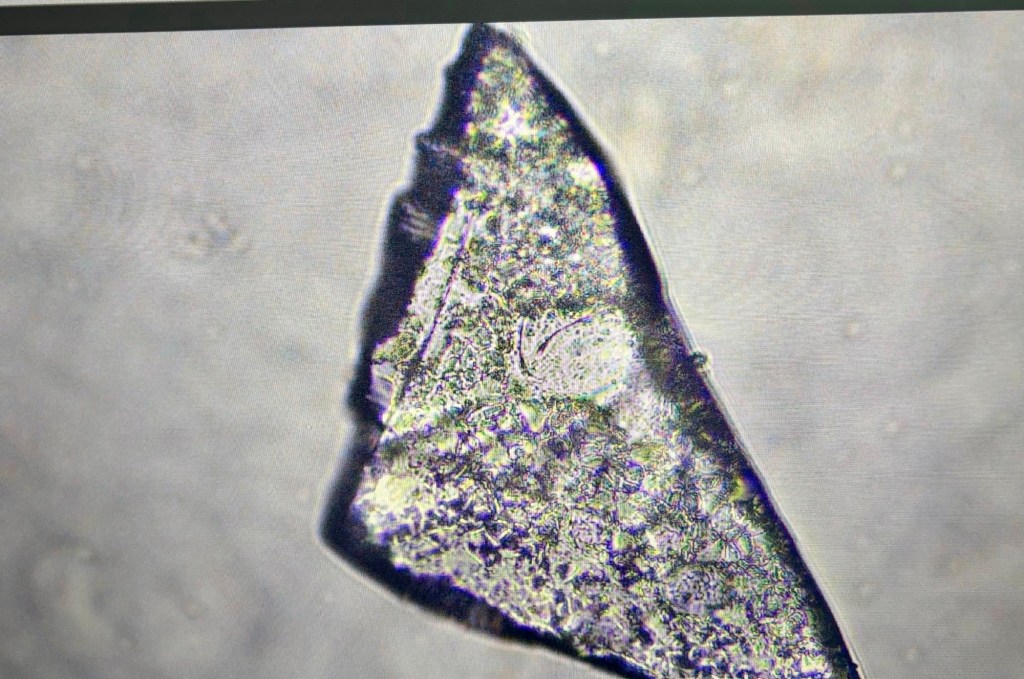

• Hoy, observar por microscopios la sangre de los inoculados, incluso la de la gente que, como condición para conservar sus empleos, debían someterse a una prueba de antígenos semanal, es horrible por la presencia de estructuras extrañas, que parecen organismos como parásitos, y otros objetos que parecen navajas.

• Esta morfología [documentada con las fotos y el vídeo que complementan esta historia] se supone que la observen los tecnólogos médicos en Puerto Rico en la sangre de miles de pacientes inoculados, pero ni lo documentan ni reportan a las autoridades.